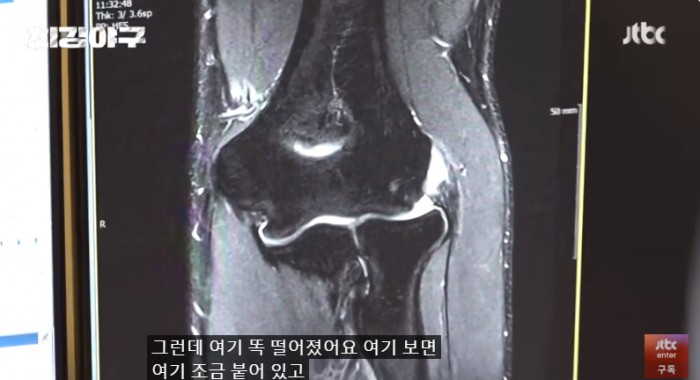

이택근이 팔 통증이 너무 심해 수술 후 타격까지 1년이 걸리는 수술을 했는데..

자신의 자리는 자신이 만들어가는 것이라는 걸 보여준 이택근의 간절함